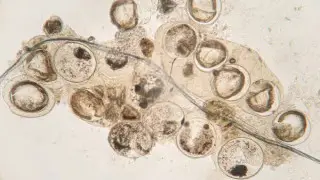

По словам инфекциониста Евгения Шаповалова, рыба нередко бывает заражена паразитами, многие из которых не видны невооруженным глазом. Стоит ли бояться есть рыбу или употребление морских обитателей не так страшно, как кажется, специалист рассказал в интервью порталу Doctorpiter, рассказывает Tengri Life.

Врач отмечает, что паразиты способны поражать как морскую, так и пресноводную рыбу.

"От охлажденной речной рыбы и красной икры можно заразиться анизакидами - возбудителями заболевания анизакидоз. При попадании в организм человека живые личинки поражают слизистые желудочно-кишечного тракта. К типичным проявлениям анизакидоза относятся тошнота, рвота, острая боль в животе. Чаще всего болезнь проходит сама: через непродолжительное время паразиты погибают и выводятся из организма", - рассказывает инфекционист.

Пресноводная рыба (щука, налим, речной окунь и другие) может быть носителем личинок широкого лентеца - возбудителя дифиллоботриоза.

"Эта опасная болезнь вызывает нарушения со стороны желудочно-кишечного тракта, а при сильном поражении способна провоцировать кишечную непроходимость. Коварство паразита еще и в том, что он может жить в организме человека невероятно долго - до 20 лет. Кроме того, лентец любит питаться витамином B12, из-за чего у пациента со временем развивается B12-дефицитная анемия. Для этого состояния характерны постоянная слабость, головокружения, нарушение чувствительности в конечностях", - предупредил специалист.

Речная рыба также может стать причиной заражения описторхозом - паразитарным заболеванием, возбудителем которого выступают личинки кошачьей двуустки.

"Этот паразит встречается в семействе карповых, в том числе в плотве, леще и язе. В организме человека червь способен паразитировать годами, поражая печень, желчный пузырь и поджелудочную железу. Осложнения у описторхоза бывают самыми серьезными, вплоть до цирроза печени, непроходимости желчевыводящих путей и злокачественных опухолей", - говорит Евгений Шаповалов.